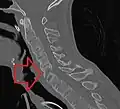

The earliest changes demonstrable by plain X-ray shows erosions and sclerosis in sacroiliac joints. Progression of the erosions leads to widening of the joint space and bony sclerosis. X-ray spine can reveal squaring of vertebrae with bony spur formation called syndesmophyte. This causes the bamboo spine appearance. A drawback of X-ray diagnosis is the signs and symptoms of AS have usually been established as long as 7–10 years prior to X-ray-evident changes occurring on a plain film X-ray, which means a delay of as long as 10 years before adequate therapies can be introduced.[24]

X-ray showing bamboo spine in a person with ankylosing spondylitis

CT scan showing bamboo spine in ankylosing spondylitis